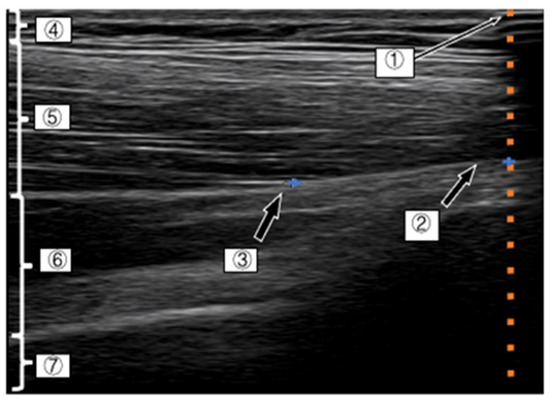

Measurement of the Index Point of the D-Fascia and Calculation of the Movement Distance